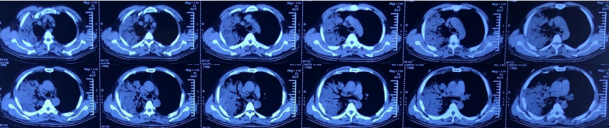

7月4日(患者入院前)胸部CT可见下肺磨玻璃渗出(图1)

图1  患者胸部CT(2019-07-04)

尿军团菌抗原(+)。入院第2天:无创机械通气通气,FiO2 100%;第3天气管插管,有创机械通气,FiO2 100%,PEEP 13 cmH2O。第4天,FiO2 45%,PEEP 8 cmH2O。逐渐降低支持力度,插管第7天撤机,拔管。拔管5天转入普通病房。整个病程中患者发热症状持续14天。患者入院前后胸部影像学变化如图2所示。